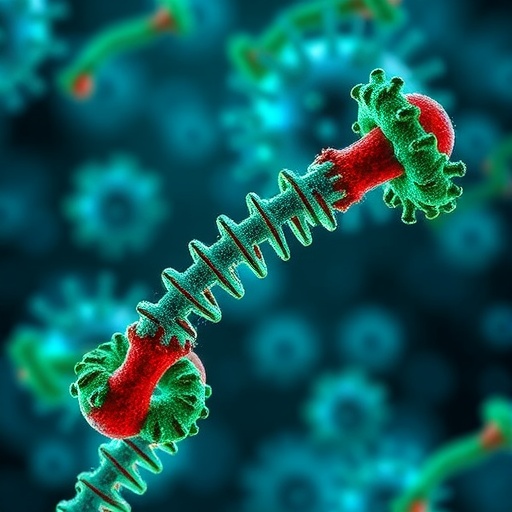

mRNA Flu Vaccine Provides Broad Immune Defense Against Diverse Influenza Strains

A groundbreaking new study conducted by researchers at Washington University School of Medicine in St. Louis illuminates the promising potential…